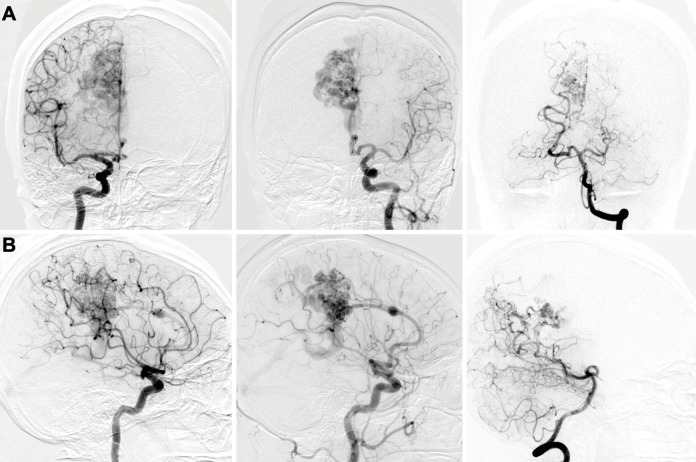

Spontaneous regression of an arteriovenous malformation (AVM) is a rare condition observed in 0.3%-1.3% of patients with AVMs and is most likely caused by hemorrhagic events. The regression of an unruptured AVM is rarer than that of a ruptured AVM. Moreover, due to its low frequency of occurrence, the etiology and natural course of spontaneous regression of an AVM is still unclear. This is the first report presenting a case of a spontaneous regression of an unruptured AVM caused by a gradual drainer vein thrombosis that was suspected to result from hypercoagulability due to protein S deficiency.